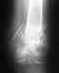

Re: Закрытый спиральный перелом нижней трети обеих костей правой голени со смещением

В общем, не все там доведено до приемлемого положения. И малоберцовая, похоже, укорочена, и межберцовое расстояние больше, чем надо, и большеберуовая неидеально сопоставлена.